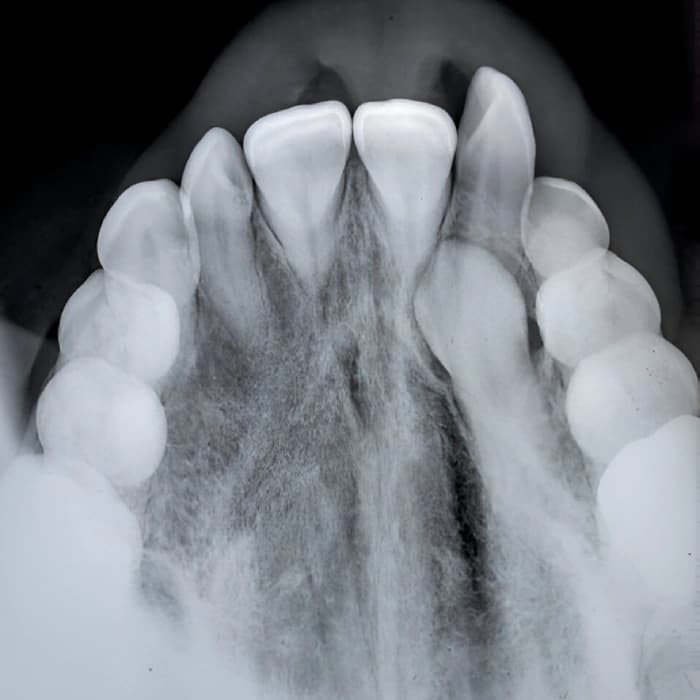

عکس بزرگ از کل سطح بالا یا پایین دندانها برای دیدن موقعیت دندانهای نهفته یا مشکلات فک

عکس اکلوزال دندان یکی از انواع رادیوگرافیهای دندانی است که بهمنظور بررسی وضعیت دندانهای خلفی، ساختار فک و دندانها و همچنین مشکلات مربوط به بایت (بستن فک) استفاده میشود. این عکس بهویژه برای ارزیابی دندانهای فک بالا و پایین که به هم برخورد دارند و بررسی پوسیدگیهای دندانی یا تغییرات ساختاری در ناحیه اکلوزال دندانها کاربرد دارد. این نوع رادیوگرافی به دندانپزشک این امکان را میدهد تا مشکلات موجود در دندانها و استخوانهای فک را شناسایی کند و درمانهای لازم را تعیین نماید.

در فرآیند گرفتن عکس اکلوزال دندان، ابتدا دندانپزشک ناحیهای که نیاز به بررسی دارد را مشخص میکند. در این روش، بیمار باید در صندلی دندانپزشکی قرار بگیرد و حسگر دیجیتال یا فیلم در نزدیکی دندانهای بالا و پایین قرار داده میشود. بیمار باید دهان خود را باز کرده و دندانهای خود را در موقعیتی خاص قرار دهد تا تصویر واضحی از ناحیه اکلوزال دندانها گرفته شود. این تصویر بهطور دقیق وضعیت دندانها و سطح تماس آنها با یکدیگر را نشان میدهد. پس از ثبت تصویر، دندانپزشک میتواند نتیجه را بررسی کرده و هرگونه مشکل یا ناهنجاری را شناسایی کند.